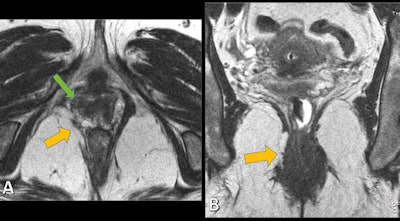

Static images lead to detection and classification of structural abnormalities, including defects in the pelvic floor anatomy, supporting structures, and anal sphincter complex. Dynamic images (during squeezing, straining, and defecation) can detect functional abnormalities that are assessed by metric measurements of the three compartments. No oral or intravenous contrast is necessary, according to the researchers.